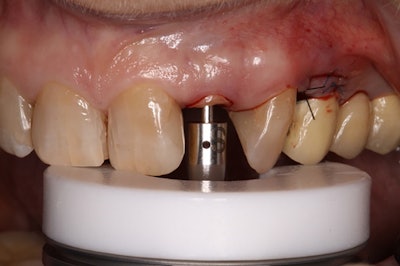

An anchor screw was positioned with the AES.